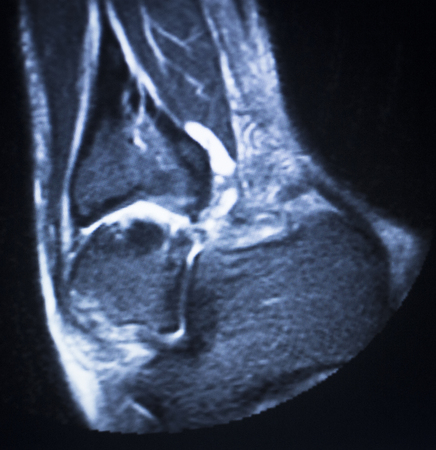

診断腱損傷のmri足首関節軸冠動脈および矢状t2のビューを比較する クローズアップのストックフォトや画像を多数ご用意 Istock

足関節mri画像正常解剖ツール 3方向 苦手な人もこれで大丈夫

症例でわかる足関節 足部のmri すぐに役立つ撮り方 読み方のポイント 羊土社